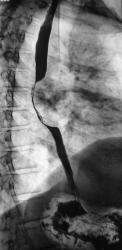

Линейные томограммы в прямой проекции

После проведенного рентгенологического исследования органов грудной полости - рентгенографии и томографии, при которой были выявлены увеличенные лимфатические узлы в корнях лёгких и средостении, было проведено рентгенотелевидение пищевода с прицельной рентгенографией и исследованием пищевода на трохоскопе, с контрастированием пищевода водной взвесью сернокислого бария "различной консистенции" - от сверхжидкого - до пастообразного, для "выяснения состояния" заднего средостения. Была зарегистрирована и документирована "локальная деформация пищевода" на протяжении 9,5 см. с перестройкой структуры "рельфа слизистой оболочки".